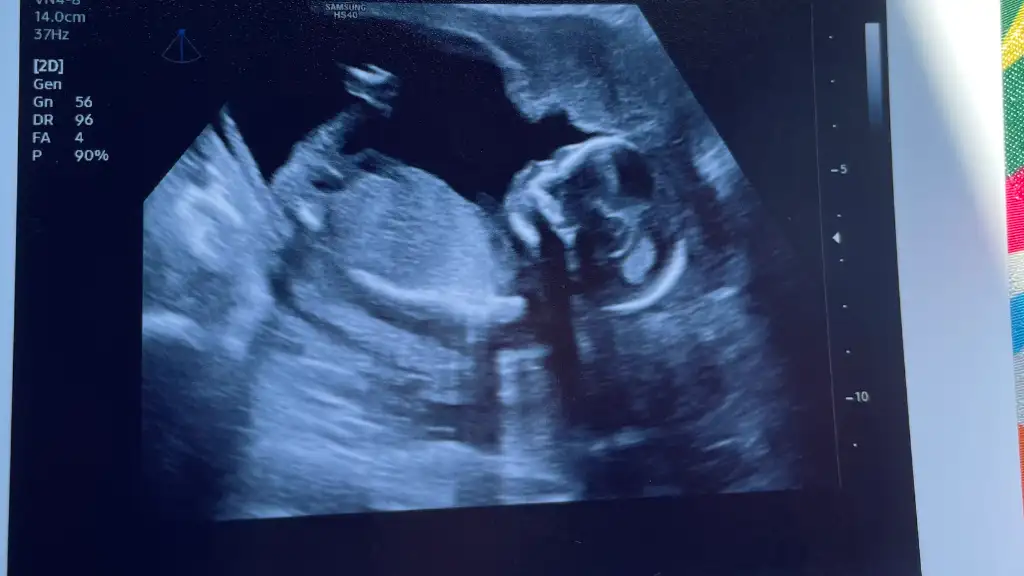

Oy maşallahBugün dr kontrolüne gittim bende oğluşum büyümüş 121gr olmuş![]()

Oyy maşallah tatlışaaa yaaBugün dr kontrolüne gittim bende oğluşum büyümüş 121gr olmuş![]()

Buraya yazacaktin sanırımBugün dr kontrolüne gittim bende oğluşum büyümüş 121gr olmuş![]()

Maşallah sağlıkla gelsin kaçıncı haftadasınız acaba birde detaylı için bişi söyledimi doktorunuz hafta olarakBugün dr kontrolüne gittim bende oğluşum büyümüş 121gr olmuş![]()